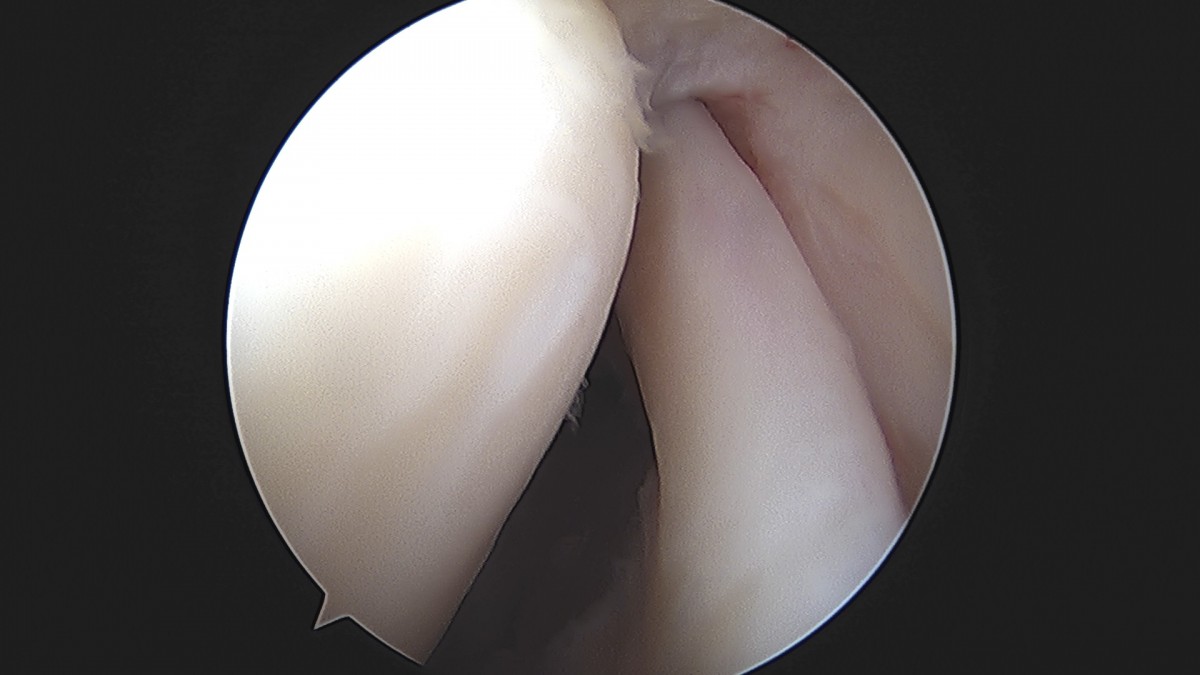

이재상원장님 어깨 견봉하 감압술 및 관절낭 이완술 주혜O 환자

dae765e4d9ac96aee867c9d6292d8784_1758003913_4176.jpg